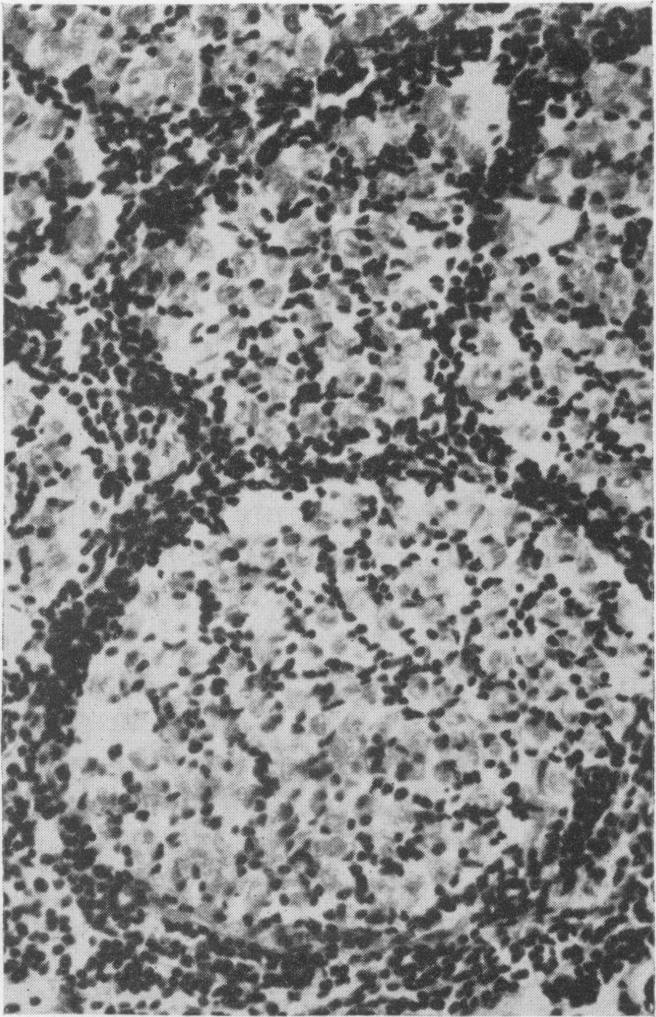

The clinical and pathological features of 63 cases of post-mortem-proved diffuse infiltration of the leptomeninges by tumour are presented. A wide variety of tumours of the nervous system, both primary and secondary, was found to give rise to such involvement, with adenocarcinoma having a particular propensity to behave in this manner. Dysfunction of cranial and spinal nerves, a confusional state and headache were prominent clinical features. Examination of the cerebro-spinal fluid was found to be less useful diagnostically in cases of primary tumours of the nervous system with leptomeningeal involvement than in cases of diffuse infiltration of the meninges by carcinoma.